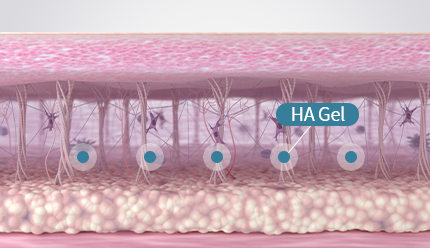

คอลลาเจน เป็นเส้นใยโปรตีนที่เป็นส่วนประกอบของผิวหนัง ช่วยยึดเกาะ

เพิ่มความยืดหยุ่นและความชุ่มชื้นแก่ผิว โดยปกติร่างกายจะสามารถผลิตคอลลาเจนได้เอง

แต่เมื่ออายุมากขึ้น ร่างกายจะสามารถสร้างคอลลาเจนได้น้อยลง

ซึ่งทำให้ผิวหนังหย่อนคล้อยและเกิดริ้วรอยตามวัยได้

ลดความหย่อนคล้อย